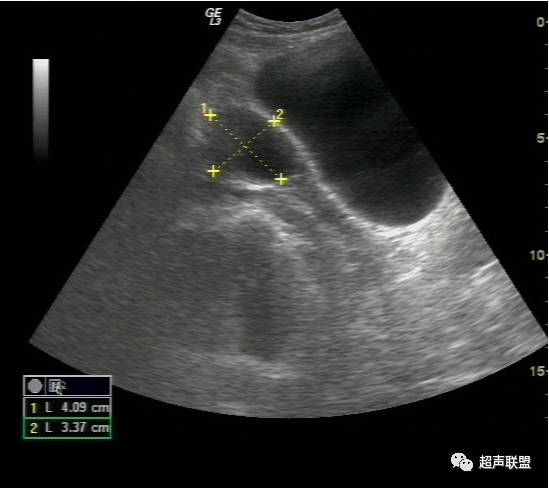

(2)一侧附件区可探及不均质包块,包块形态欠规则,边界不清楚,回声紊乱。

(3)陶氏窝:可见多少不一不规则的液性暗区,暗区中有密集点状回声。

宫外孕破裂出血的声像图 宫外孕发生率占妊娠的0.5%~1%,其中95%为输卵管妊娠。常与输卵管炎、输卵管手术后输卵管不同程度粘连、受精卵移行不畅有关。输卵管妊娠时由于缺乏完整蜕膜,孕卵植入后,其绒毛借蛋白分解酶的作用直接侵蚀管壁肌层,因输卵管管壁薄弱,不能适应受精卵的发育,当受精卵发育到一定程度后,常引起流产或破裂。由于输卵管肌层血管丰富,短期内即可大量出血使患者陷入休克。由于破裂口周围形成凝血块或未凝血液,从而超声表现为形态不规整、边界不清楚、回声紊乱的混合性包块,并有盆腔积液,积液中含血细胞形成的密集点状回声。

宫外孕破裂出血是妇产科最常见的急腹症之一。出血量大者,病情特别危急,需要立即作出诊断和鉴别诊断,以便采取适当而有效的治疗措施。对于一个临床主要表现为下腹剧痛,超声表现为:子宫轻度增大,子宫内膜不同程度增厚,宫内未见妊娠囊;一侧附件区可探及不均质包块,包块形态欠规则,边界不清楚,回声紊乱;陶氏窝可见多少不一不规则的液性暗区,暗区中有密集点状回声。盆腔甚至腹腔积液的妇产科急症患者。检查者应该想到上述疾病。并尽可能详细询问月经史、性生活史及临床病史,结合尿或血HCG检查、血常规检查等,进行综合分析判断。随着超声仪技术的发展,阴道彩色多普勒检查的应用,宫外孕包块内滋养层血流的检测,将更有助于宫外孕破裂的诊断及鉴别诊断。